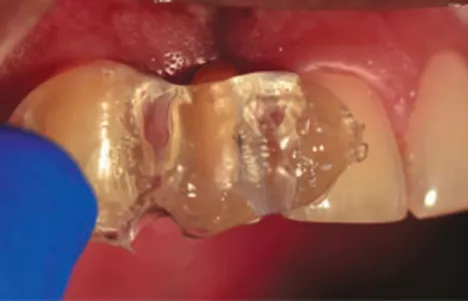

FIG 6:

The extracted lateral incisor shown here in the process of being cut and contoured to size to be used as a Natural Tooth Pontic which will be cleaned and filled from the cervical/apical area with composite resin.